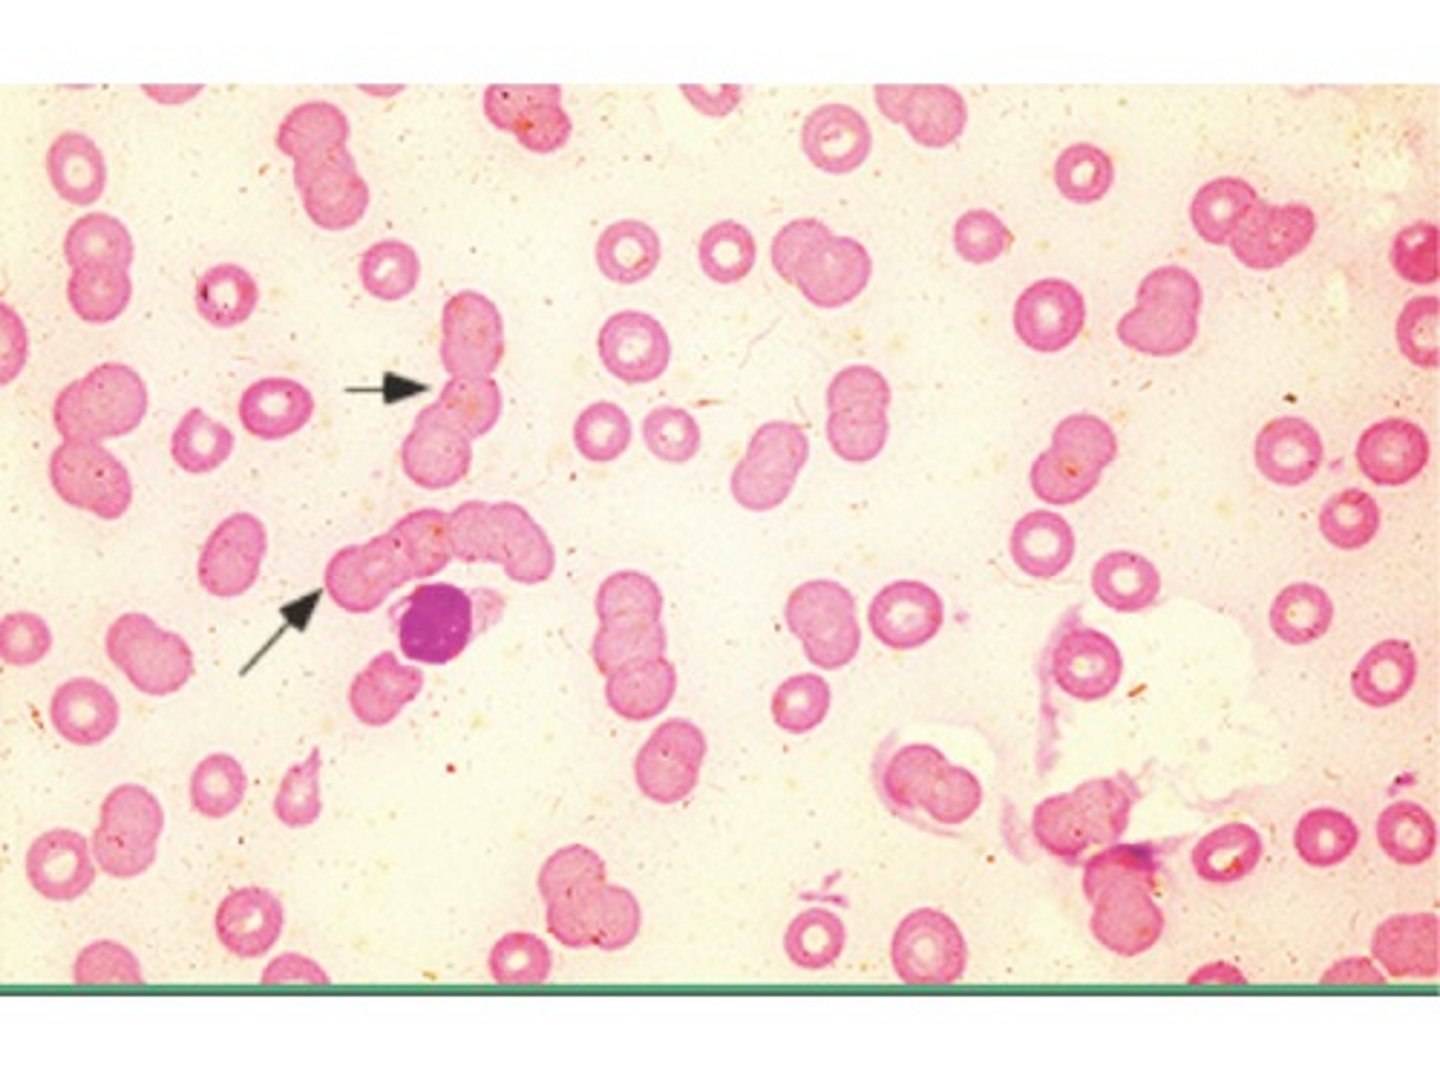

hypochromasia

increased level of central pallor

-decrease hemoglobin concentration

torocytes

AKA punched out cells

- "donut" hole presentation

--artifact